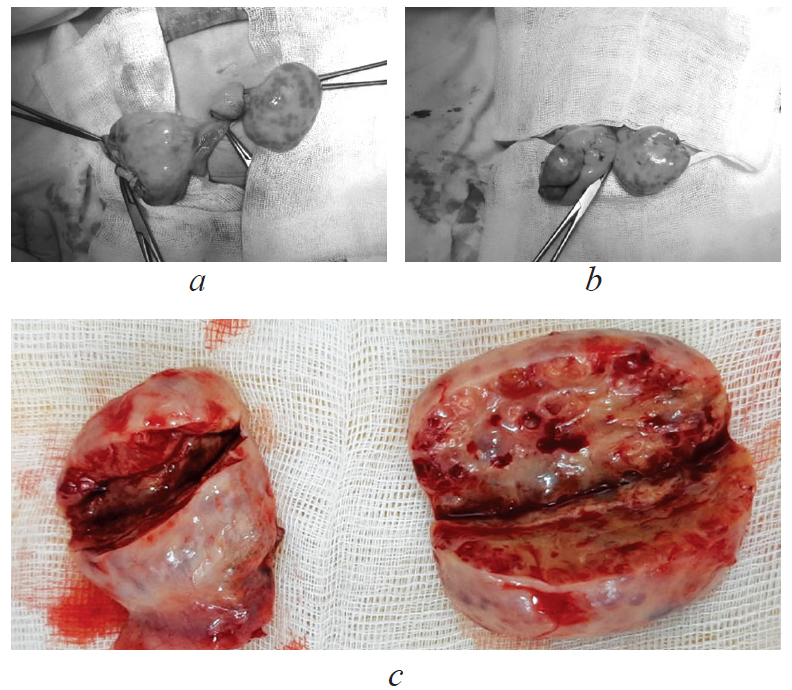

We present a rare clinical case of a complicated course of Donohue syndrome, diagnosed in a 2-month-old patient. A feature of this clinical case was the giant growing multifollicular ovaries, which became an absolute indication for organ resection surgery.